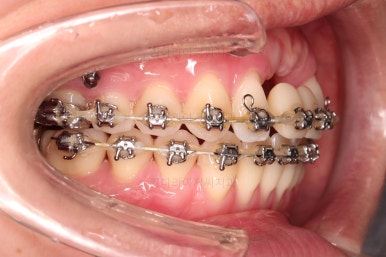

3. 치료과정

개방교합을 닫는 전략은 앞니를 약간 끌어내리고, 어금니를 앞니 위치로 약간 올려서 균형을 맞추는 건데요.

장치 부착은 윗니 어금니부터 했습니다.

미니스크류를 다양하게 활용하여 어금니 높이를 조절합니다.

여전히 앞니는 내버려둔 채로, 윗니는 어금니쪽만 진행하며 아랫니도 장치를 부착했습니다.

난이도가 매우 높은 치료인만큼 미니스크류의 구성과 장치 구성도 매우 복잡했는데요.

윗니 어금니를 뒤로 밀면서 앵글씨 2급 부정교합을 개선해 주고, 높낮이를 조절하면서 개방교합을 개선해 줍니다.